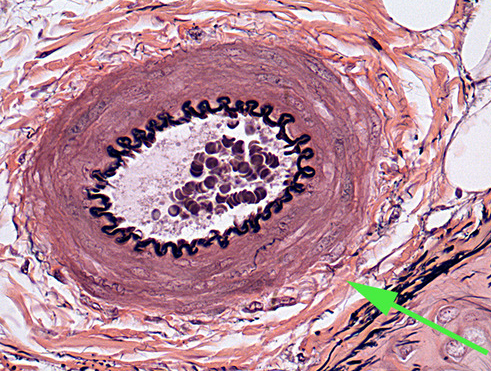

What is the name of the layer indicated by the green arrow? endothelium

The black twisted line is elastic tissue found in elastic arteries. The squiggly line is called the internal elastic membrane.

What is the name of the layer indicated by the green arrow? tunica externa